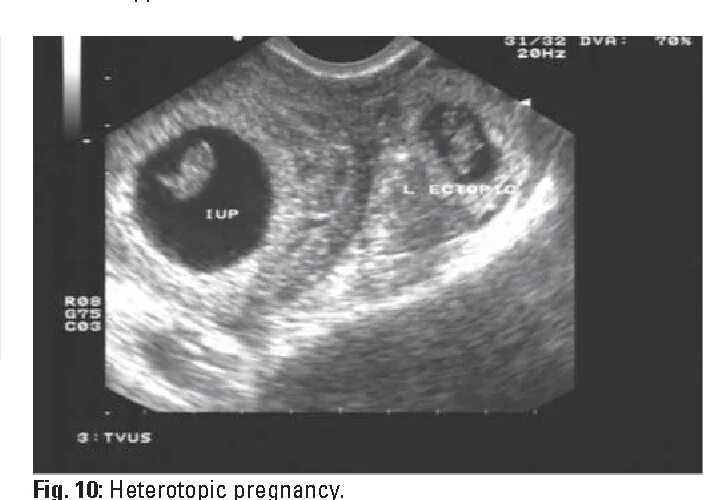

Можно ли на узи увидеть внематочную беременность